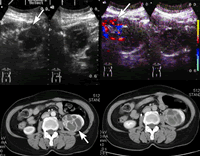

图1 B型超声声像图,示左肾下极囊实性肿物,向肾外凸出(箭号),实性部分低回声,囊性部分呈分隔状。

图2 多普勒彩色血流图,可见肿瘤实性部分内血流。

图3 增强CT扫描肾皮质期

图4 增强CT扫描肾实质期